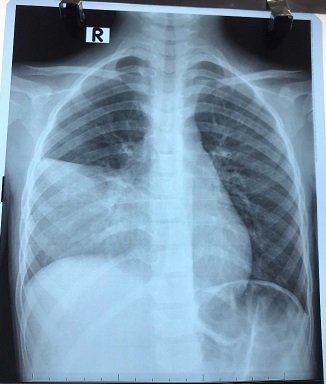

Viêm phổi do Mycoplasma pneumoniae có thể từ từ và bán cấp, trẻ có thể sốt nhẹ sau đó tiến triển thành sốt cao hơn và ho dai dẳng. Thời gian ủ bệnh có thể từ 2-3 tuần. Khởi đầu trẻ có thể có những triệu chứng ở đường hô hấp trên như: ho, hắt hơi, sổ mũi, sốt nhẹ. Sau đó bệnh có thể tiến triển hoặc gây biến chứng viêm phổi dẫn đến tình trạng sốt cao, ho kéo dài liên tục, khó thở, một số trẻ lớn có thể khởi phát cơn hen cấp tính hoặc có thêm các triệu chứng khác không điển hình như đau đầu, đau cơ, đau ngực,…

Các biến chứng nghiêm trọng thường không phổ biến, nhưng có thể dẫn đến trẻ phải nhập viện và đôi khi tử vong. Các biến chứng bao gồm: Viêm phổi nặng, khởi phát đợt cấp của hen phế quản, viêm não, thiếu máu tan máu, suy thận, hội chứng Stevens-Johnson…